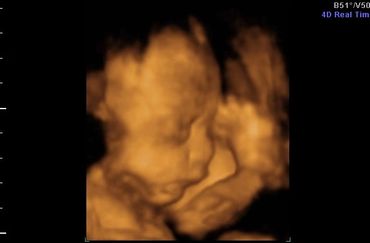

All our providers do their own ultrasounds in the office during your visit. We are known for our ultrasounds and do at least four with each pregnancy. And we can record your ultrasound on a USB device for you to take home and share!